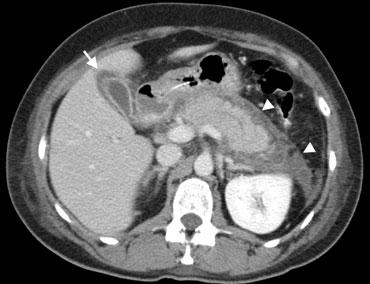

Bên trái là hình ảnh của bệnh nhân nam 62 tuổi với viêm túi mật cấp có sỏi.

Siêu âm cắt ngang tại vị trí đau tối đa cho thấy túi mật căng giãn do ứ dịch, thành dày, không thể ép xẹp (đầu mũi tên), với sỏi trong lòng túi mật và cặn lắng hoặc mảnh vụn.

CT có thuốc cản quang cho thấy viêm mỡ lan rộng (đầu mũi tên) bao quanh túi mật (mũi tên).